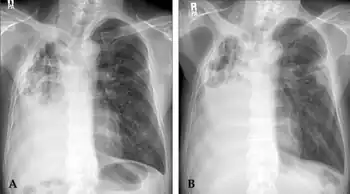

Radiographic findings with M. xenopi pulmonary disease are variable but most often include upper lobe cavitary abnormalities similar to tuberculosis.